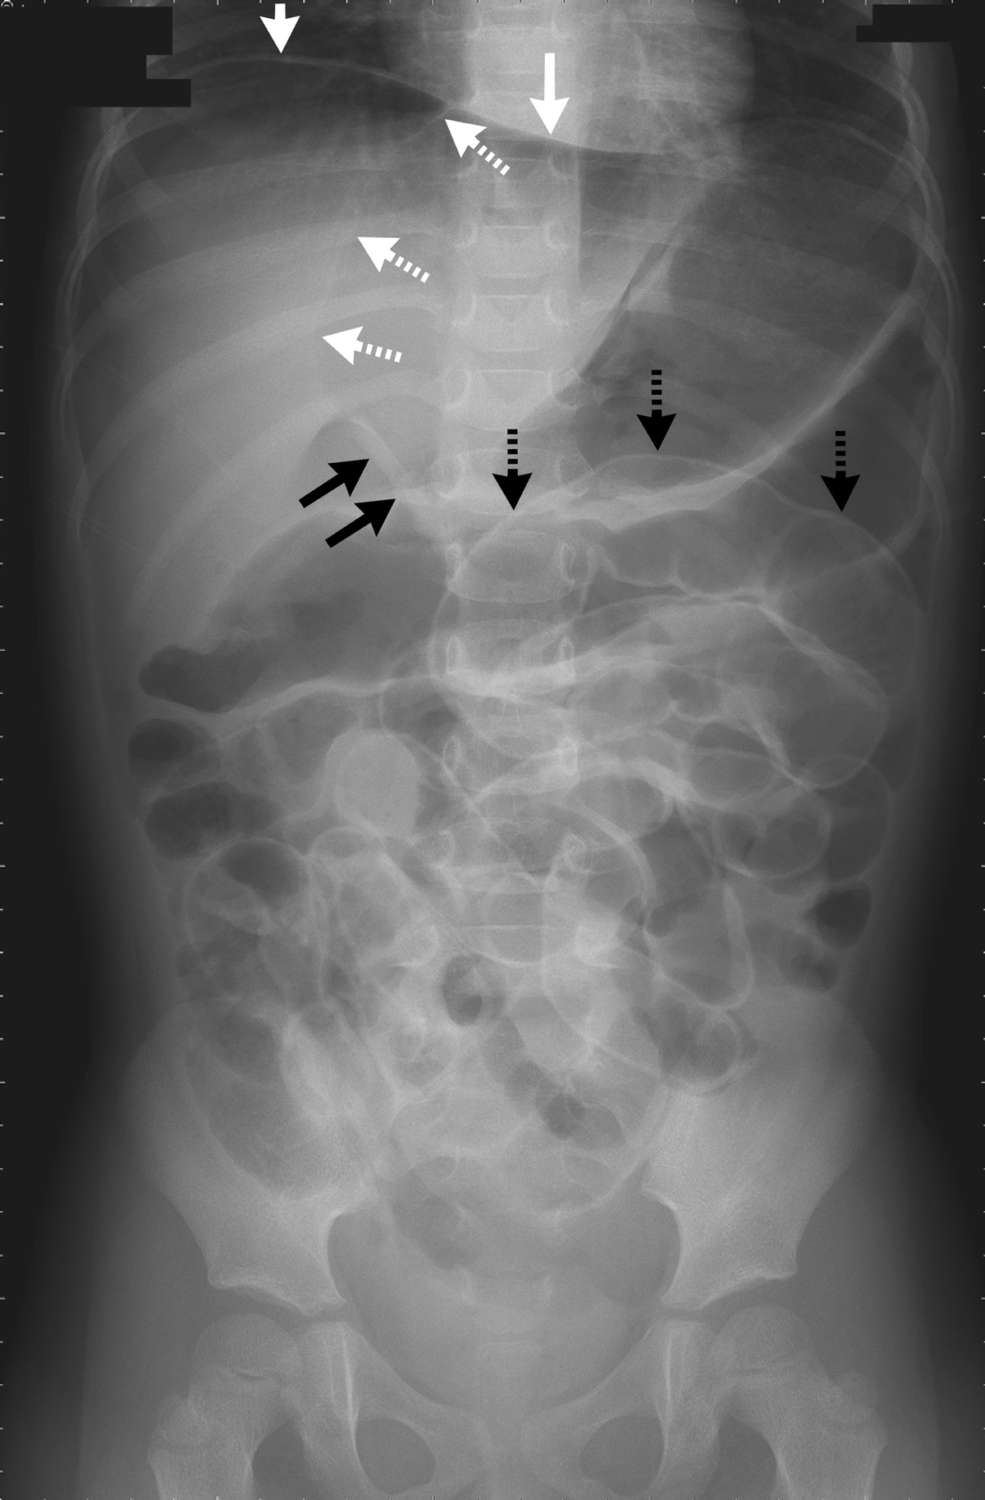

The laboratory evaluation revealed a white-cell count of 5000 per cubic millimeter, with 63% segmented neutrophils. The plain-film radiograph of the abdomen showed several signs of free intraperitoneal gas.

These included air accumulation in the right upper quadrant (the subphrenic area and ventral surface of the liver) (solid white arrows); the falciform-ligament sign, visible as a longitudinal linear density on the ventral surface of the liver (dashed white arrows); the ligamentum teres sign, visible as a linear density running along the inferior edge of the falciform ligament (solid black arrows); and Rigler’s sign, the visualization of air on both sides of the bowel wall (dashed black arrows). All these signs indicated pneumoperitoneum.